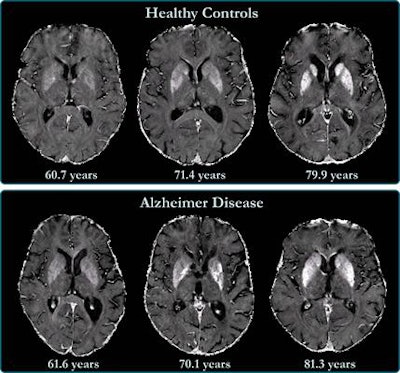

Previous studies have linked high levels of brain iron with Alzheimer's disease, wrote a team led by Dr. Anna Damulina, also of the university: Iron deposits are associated with beta amyloid, a protein that forms plaques between neurons and disrupts brain function, as well as tangles of another protein called tau that also collects inside neurons. But these studies have focused on the deep gray-matter structures of patients with Alzheimer's disease rather than the outer layer of the brain called the neocortex.

Unfortunately, the neocortex can be challenging to image with MRI, since the area's anatomy may make MRI susceptible to distortions, according to Damulina and colleagues. The best way to address this limitation is to use ultrahigh-resolution scans, but these can take too much time in the clinical setting.

So the researchers assessed baseline levels of brain iron in 100 patients with Alzheimer's disease and 100 healthy controls using a more efficient combination of a 3-tesla MR scanner and a technique called R2* mapping, which detects increased iron concentrations in the body (higher values translate to higher levels of iron).

The study found higher iron deposits in the Alzheimer's patients' deep gray matter, total neocortex, and in the temporal and occipital lobes compared to healthy controls.